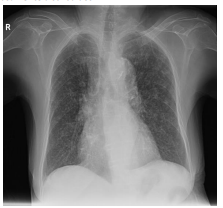

Uma mulher de 40 anos, com sintomas respiratórios e

emagrrecimento apresenta alterações em radiografia de

tórax,em posição póstero-anterior, compatíveis com padrão

miliar (imagem).

Em relação a este padrão, considere os itens a seguir.

I. Representam tênues opacidades nodulares agrupadas, de difícil visualização, localizadas nas regiões apicais e axilares

II. Representam opacidade lobar associada a linhas que convergem para o hilo (convergência hilar)

III. Representam micronódulos entre 2 e 3mm de diâmetro difusamente distribuídos

"https://radiopaedia.org/?lang=us">Radiopaedia.org. From the case <ahttps://radiopaedia.org/cases/31375?lang=us">rID: 31375</a>

Está correto o que se afirma em